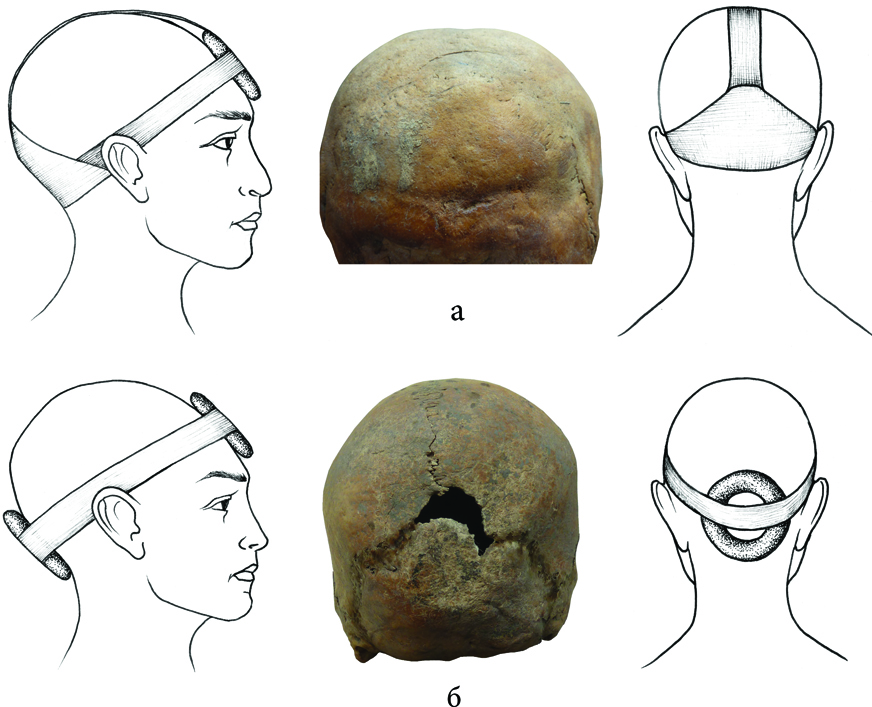

Однако медицинская практика древности не может не вызывать удивления. Во многих захоронениях бронзового века обнаруживают черепа со следами трепанации. Причем эта операция делалась двумя методами – в одних случаях в черепе проделывали одно отверстие, в других – два. По состоянию костей можно даже определить диагноз – в одном из трепанированных черепов следы воспаления среднего уха. В другом захоронении был найден череп со следами ранения и трепанации, сделанной, по-видимому, для оказания медицинской помощи воину. Предположений относительно того, что трепанировали черепа умерших, не возникает, поскольку на костях черепов видны следы заживления. Люди, перенесшие эту сложную операцию, какое-то время жили. Профессии врача тогда еще не было, хирургией занимались жрецы, которые считались не только уважаемыми, но самыми знающими людьми племени.

Любопытно, что врачи нашего времени, хотя и располагают современным хирургическим оборудованием, но используют те же принципы трепанации, что и их далекие предки во II тысячелетии до нашей эры. На территории современной Армении обнаружено несколько центров, в которых проводили трепанацию черепа, один из таких центров был обнаружен в Лори, в селе Шнох. Там же находят и древние хирургические инструменты, используемые при проведении операций (Лори Берд). Причем трепанированные черепа в нашем регионе находят только в Армении. Но как решалась проблема анестезии? По мнению Анаит Худавердян, больным давали вино с растительными обезболивающими средствами, вероятно, это был специальный состав, изготовленный на основе ядовитых грибов.

В Европе черепа со следами трепанации тоже находят, но трепанации были символическими и проводилась и как мистический ритуал, и в медицинских целях. Кроме территории современной Армении медицинские трепанации проводились также у инков – американских индейцев, но это происходило в гораздо более поздний период. Правда, ученым известны и неудачные случаи трепанации. В одном из захоронений в Армении был обнаружен череп взрослого человека (могильник Багери чала) со следами незавершенной трепанации. По-видимому, больной умер во время операции в результате, как теперь принято говорить, врачебной ошибки, о чем свидетельствует состояние черепа.

И еще один любопытный факт, обнаруженный в процессе исследований. При раскопках ученые находят черепа со следами искусственной деформации. Начиная с V тысячелетия до нашей эры специальные приспособления — обычно дощечки и плотные ткани закреплялись на голове еще в младенческом возрасте. Их носили примерно до 18 лет, что способствовало формированию вытянутой формы черепа. Эпоха античности была непростым, насыщенным событиями временем. Сюда приходили иранские племена – саки и скифы. По мнению Анаит Худавердян, искусственная деформация черепа не была данью принятым тогда представлениям о красоте и, возможно, особая, вытянутая форма черепа должна была отличать местное население от пришельцев. Но по сравнению с тем, что происходило в это же время на территории Грузии, где тоже встречается множество деформированных черепов, здесь процедура деформации проводилась значительно более щадящими методами.